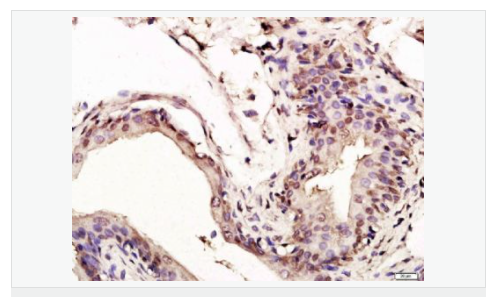

image.png